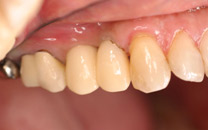

術後 |

![]() |

ソケットリフトもおこないました。 |